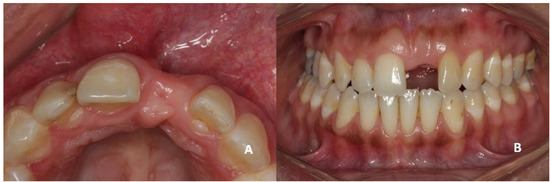

On clinical inspection of the aesthetic area, it was observed in all patients that the integrity of the vestibular plate was compromised by significant physiological and structural changes after extraction (Figure 1). This was verified through periapical radiographs and/or panoramic and dental CBCT, which provided sagittal and frontal slices for analysis. On sagittal CBCT images, the anteroposterior distance of the CNP at the level of its upper, middle, and lower thirds was calculated. Axial plane images were in turn used to determine NPC height from the level of the upper bifurcation to the palatal opening, and the width of the residual crest in the toothless zone [24,25].

Figure 1.

(A,B) Initial presentation of a patient wearing a removable partial prosthesis replacing a missing left upper central incisor.